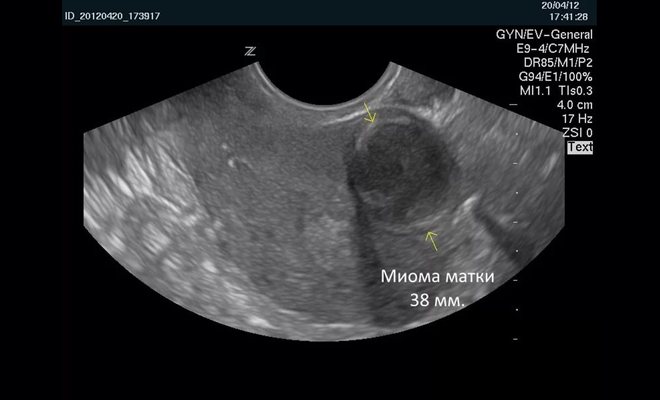

Врач-сонолог определяет миому как округлый объект с гетерогенной структурой и чёткими границами, делающими сигнал датчика слабее.

Интрамуральный узел

Находящийся в структуре маточной стенки узел принято называть интрамуральным. Он располагается в проекции миометрия и обычно не приводит к деформации маточных стенок или контуров полости. Выделяют мелкие (8 – 15 мм), средние (15 – 35 мм) и крупные (35 – 70 мм) интрамуральные узлы.

Фото 2. Заключение. Расшифровка.

Во время обследования специалист обращает внимание на эхопризнаки миомы матки – локальное уплотнение стенки. Структура опухоли несколько отличается от остального миометрия. Внешний край остается четким, он может выпирать как в просвет матки, так и в брюшную полость. Эхогенность новообразования умеренно сниженная. Пример можно увидеть на следующем фото.